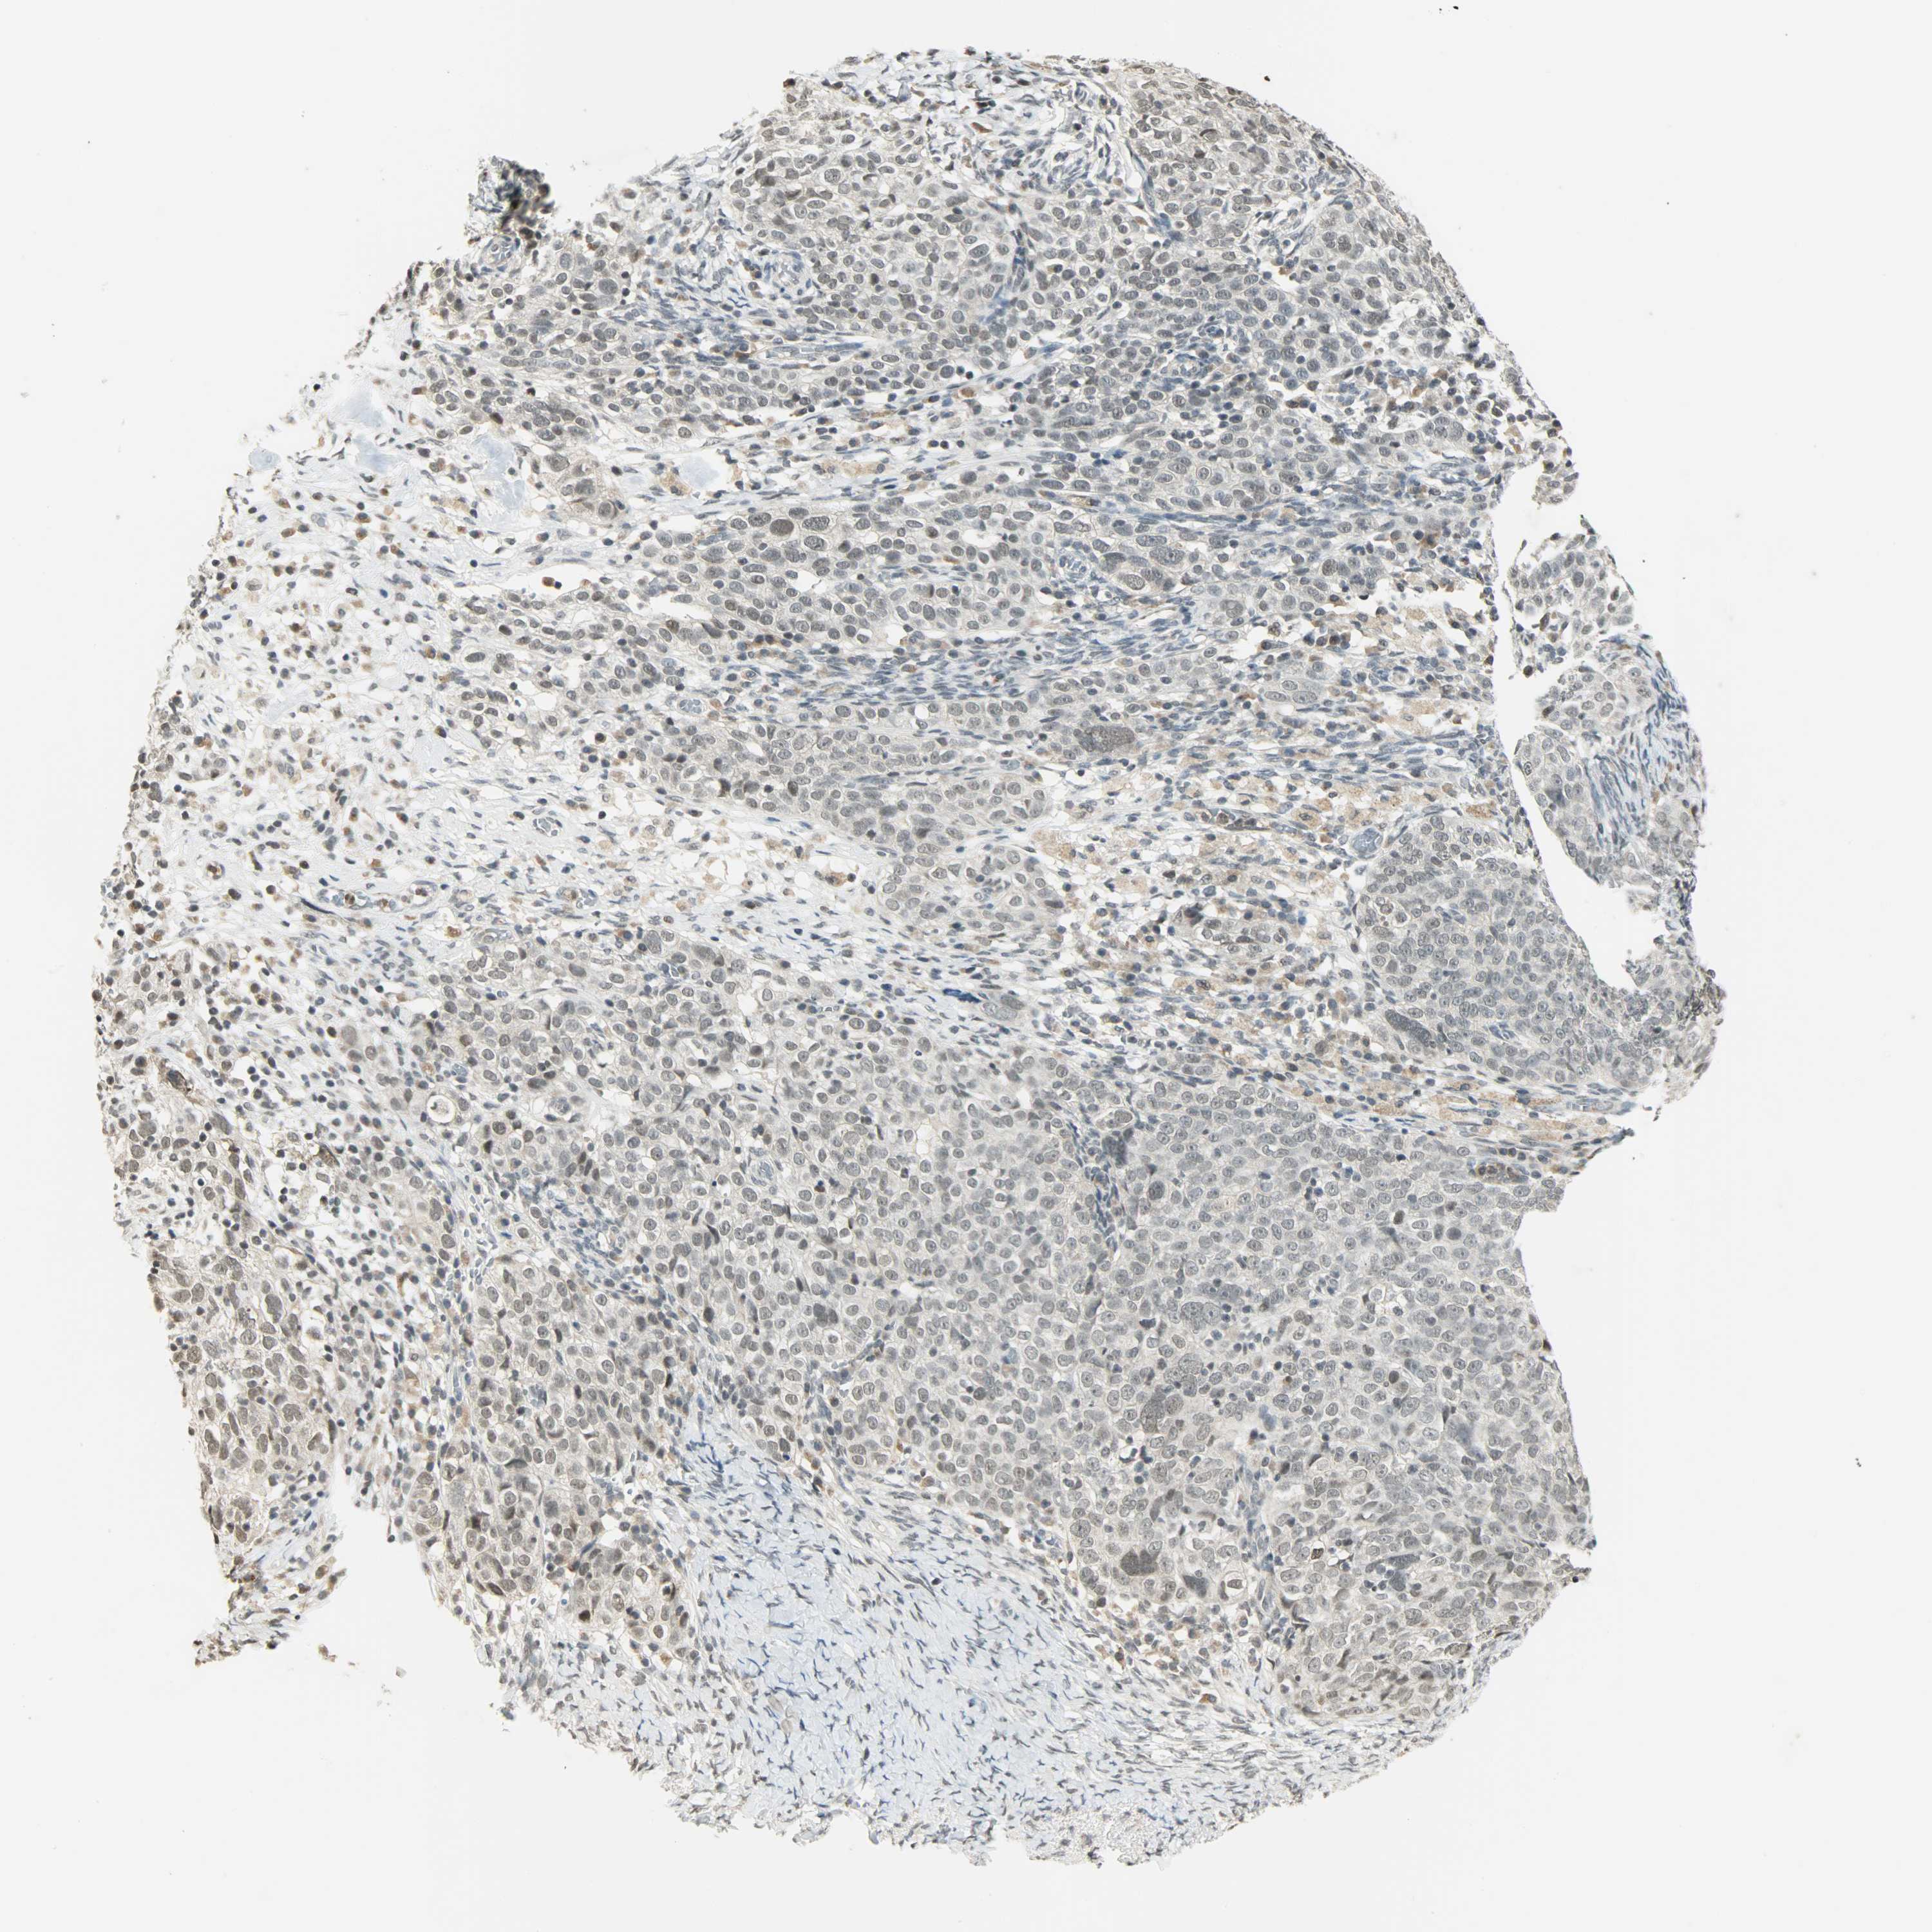

OVARIAN CANCER - Protein expressioni

A mouse-over function shows sample information and annotation data. Click on an image to view it in a full screen mode. Samples can be filtered based on level of antibody staining by selecting one or several of the following categories: high, medium, low and not detected. The assay and annotation is described here.

Note that samples used for immunohistochemistry by the Human Protein Atlas do not correspond to samples in the TCGA dataset.

Antibody stainingi

Antibody staining in the annotated cell types in the current human tissue is reported as not detected, low, medium, or high, based on conventional immunohistochemistry profiling in selected tissues. This score is based on the combination of the staining intensity and fraction of stained cells.

Each image is clickable and will lead to virtual microscopy that enables deeper exploration of all samples and also displays staining intensity scores, fraction scores and subcellular localization as well as patient and tissue information for each sample.

Antibody CAB005227

Cystadenocarcinoma, serous, NOS